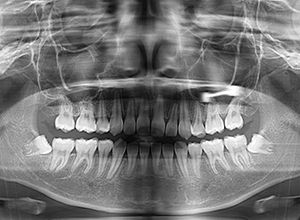

| パノラマ所見 | 上顎両側第三大臼歯は欠損、下顎第三大臼歯は埋伏していた。 |